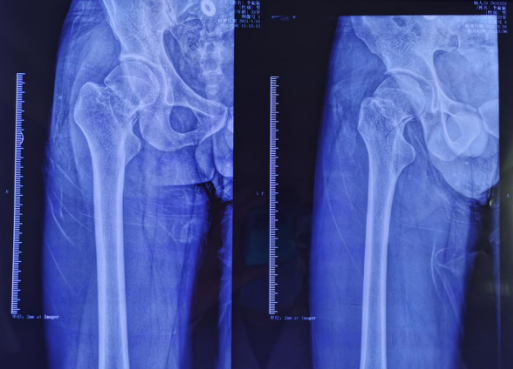

术前影像

关节科、运动医学科张传开主任给患者完善相关检查,该患者的各项指征符合进行股骨颈骨折机器人手术的要求。